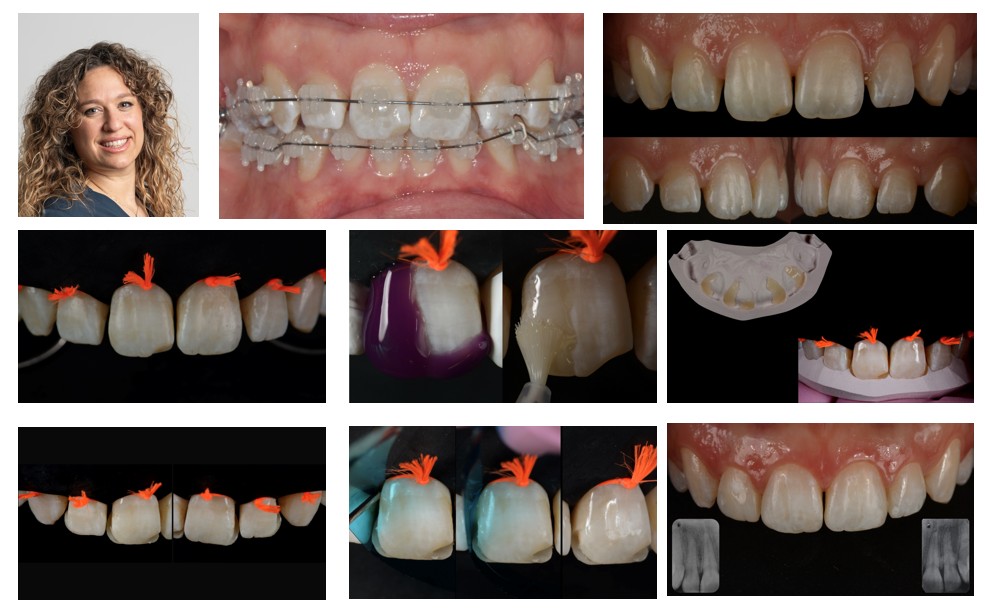

2. Dr. Allegra COMBA (IT)

Tooth Shape Management in Post-Orthodontic Patients:

A Conservative Approach

Saturday, May 30th 2026 11:30 - 12:00

Orthodontic therapy establishes alignment, occlusal balance, and spatial harmony within the dental arches. However, in some cases, orthodontic correction alone may not be sufficient to achieve the optimal esthetic result. Tooth shape anomalies, size discrepancies, and subtle morphological disharmonies can persist after treatment, potentially influencing both smile esthetics and long-term stability.

In these situations, a minimally invasive combined orthodontic–restorative approach allows the clinician to complete and refine the case. Additive adhesive procedures, guided by careful esthetic and functional planning, enable correction of morphological discrepancies while preserving maximum enamel and maintaining occlusal integrity.

Particular attention will be given to young patients, in whom preservation of sound dental tissue is essential. Through clinical cases, the lecture will demonstrate how interdisciplinary planning and conservative restorative strategies can enhance smile harmony and ensure predictable, long-lasting outcomes.